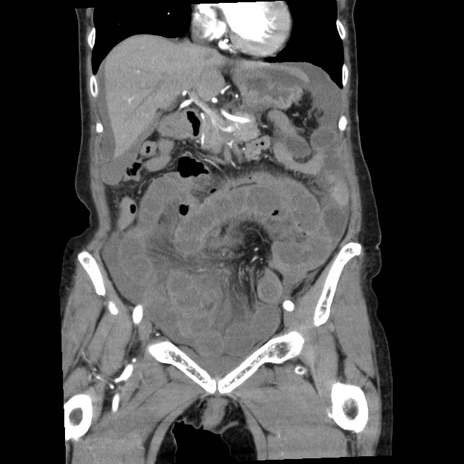

症例1(冠状断像)

【症例】80歳代女性

【主訴】腹痛

【現病歴】8時間前から腹痛あり来院。

【既往歴】糖尿病、脂質異常症、子宮体癌にて子宮全摘術

【身体所見】意識清明・会話良好だが腹痛で苦悶様、全腹部にわたって反跳痛と圧痛あり

【データ】WBC 13600、CRP 0.14、LDH 224、CK 90